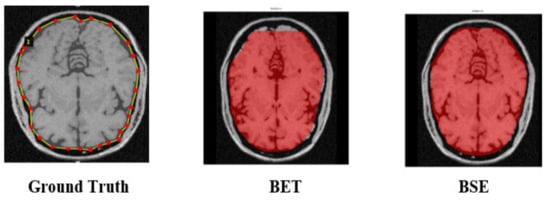

3.2. Ground Truth and Baseline Experiments

We employed two state-of-the-art image segmentation methods, viz., BET and BSE for generating baseline values of brain MR images to understand the effectiveness and precision of our experimented method. BET is a traditional method widely used for skull stripping. It segments the brain tissues from the non-brain tissues by using features such as intensity, shape, and contrast of brain MR images [53]. BSE is also a traditional method that uses several filters, edges, detection, and morphological operations to extract the surface of brain MR images [6]. We created ground truth (GT) by contouring the cerebrum area using polygonal labeling. Moreover, we segmented the same brain MR image using BET and BSE techniques. We treated selected brain MR images to remove noise because both baseline methods require noise-free images. BET utilizes a deformable model to segment the input MR image while using a non-linear smoothness technique for noise treatment. BSE combines edge detection and morphology-based techniques to segment the input MR image using an anisotropic diffusion technique for noise treatment. Contrary to this, the Mask–RCNN-based experimental method does not require noise treatment. Figure 4 depicts the output of baseline segmentation.

Figure 4. Generation of baseline segmentation results for Ground Truth and comparison of results.